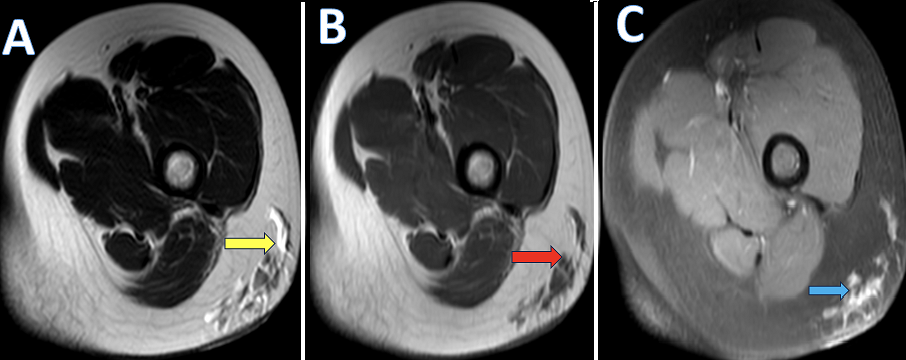

A 12-year-old female presented to the dermatology department with a history of gradually progressive swelling over the posterolateral aspect of the left thigh for the past six months. The overlying skin appeared normal without discoloration or ulceration. Neurovascular examination of the limb was normal. Contrast-enhanced magnetic resonance imaging (MRI) of the left thigh revealed multiple, well-defined cystic lesions within the subcutaneous plane of the posterolateral aspect of the left thigh. These lesions appeared hyperintense on T2 and T2 fat-suppressed sequences, hypointense on T1, and showed minimal thin peripheral enhancement following contrast administration. No diffusion restriction on DWI images. The underlying muscles, myofascial planes, femoral cortex, and neurovascular bundles were intact. The lesions collectively measured approximately 2.2 x 2.6 x 3 cm (AP X TR X CC). Ultrasonography was done for correlation of the left thigh, which shows a well-defined, multiloculated cystic lesion confined to the subcutaneous plane. The lesion showed multiple thin internal septations with anechoic contents and no significant internal vascularity on Doppler. Based on the combined radiological findings, the final diagnosis of lymphangioma circumscriptum of the left thigh was made. The patient was referred to pediatric surgery for further evaluation. Surgical excision was planned due to progressive enlargement and cosmetic concerns. Complete excision of the superficial lesion was performed. Histopathological examination confirmed the diagnosis of lymphangioma circumscriptum of the left thigh. The postoperative period was uneventful. At short-term follow-up (3months), there was satisfactory wound healing with no evidence of recurrence.